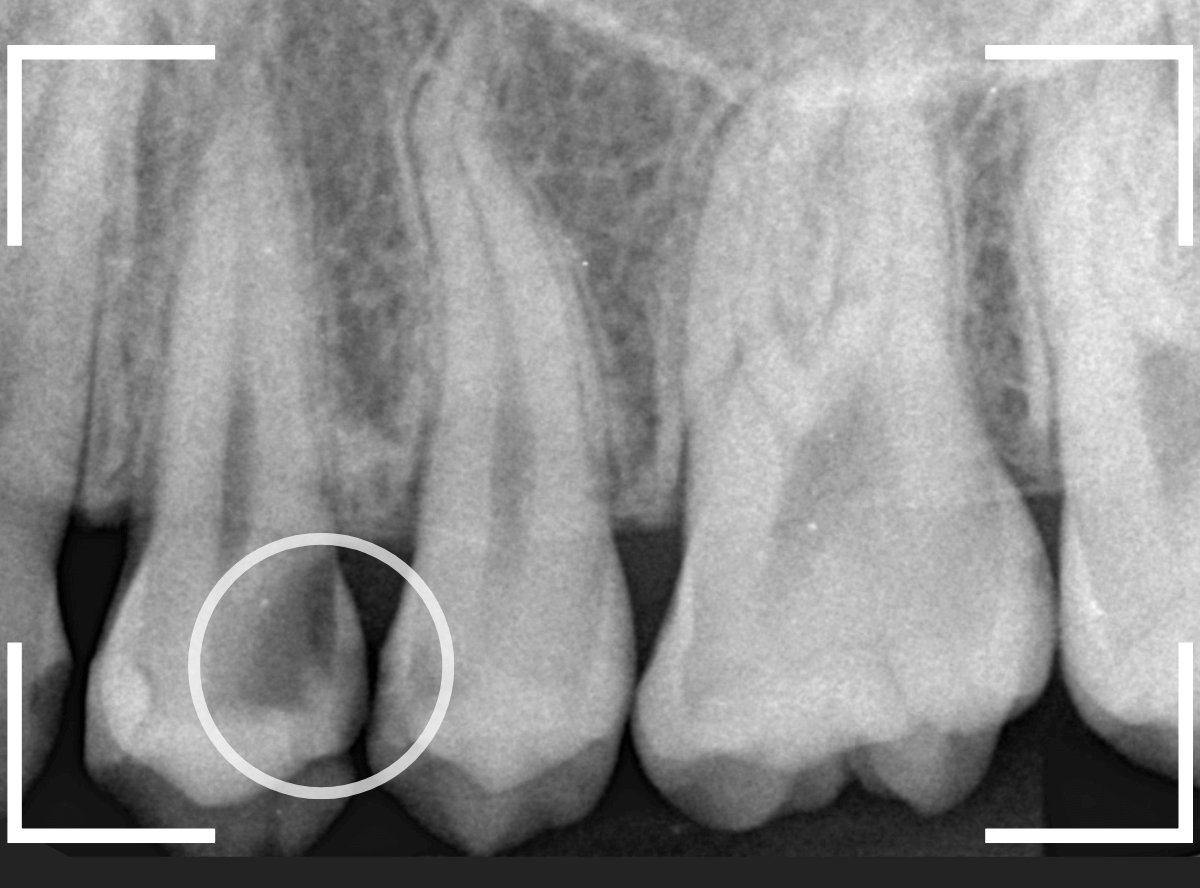

Case.26 <動画編> 症状もなく、深く進行する「歯と歯の間の虫歯治療」

今回は、歯と歯の間で大きな虫歯が進行しているケースです。

見た目に虫歯は見当たらず、痛みもありませんが、レントゲン写真で確認すると、歯と歯の間から、歯の神経まで達するほど虫歯が広がっています。

これほど大きな虫歯でも、症状がない事は多くあります。

検査時に〇部、歯と歯の間の小臼歯部に虫歯らしき黒い影があるのが見つかりました。

かなり怪しいですが、メタル・インレーが入ってるので、それが透けている可能性もあります。

レントゲン写真で確認します。

レントゲンでは後ろの大臼歯部の方が虫歯になっているように見え、小臼歯部は問題ないように見えます。